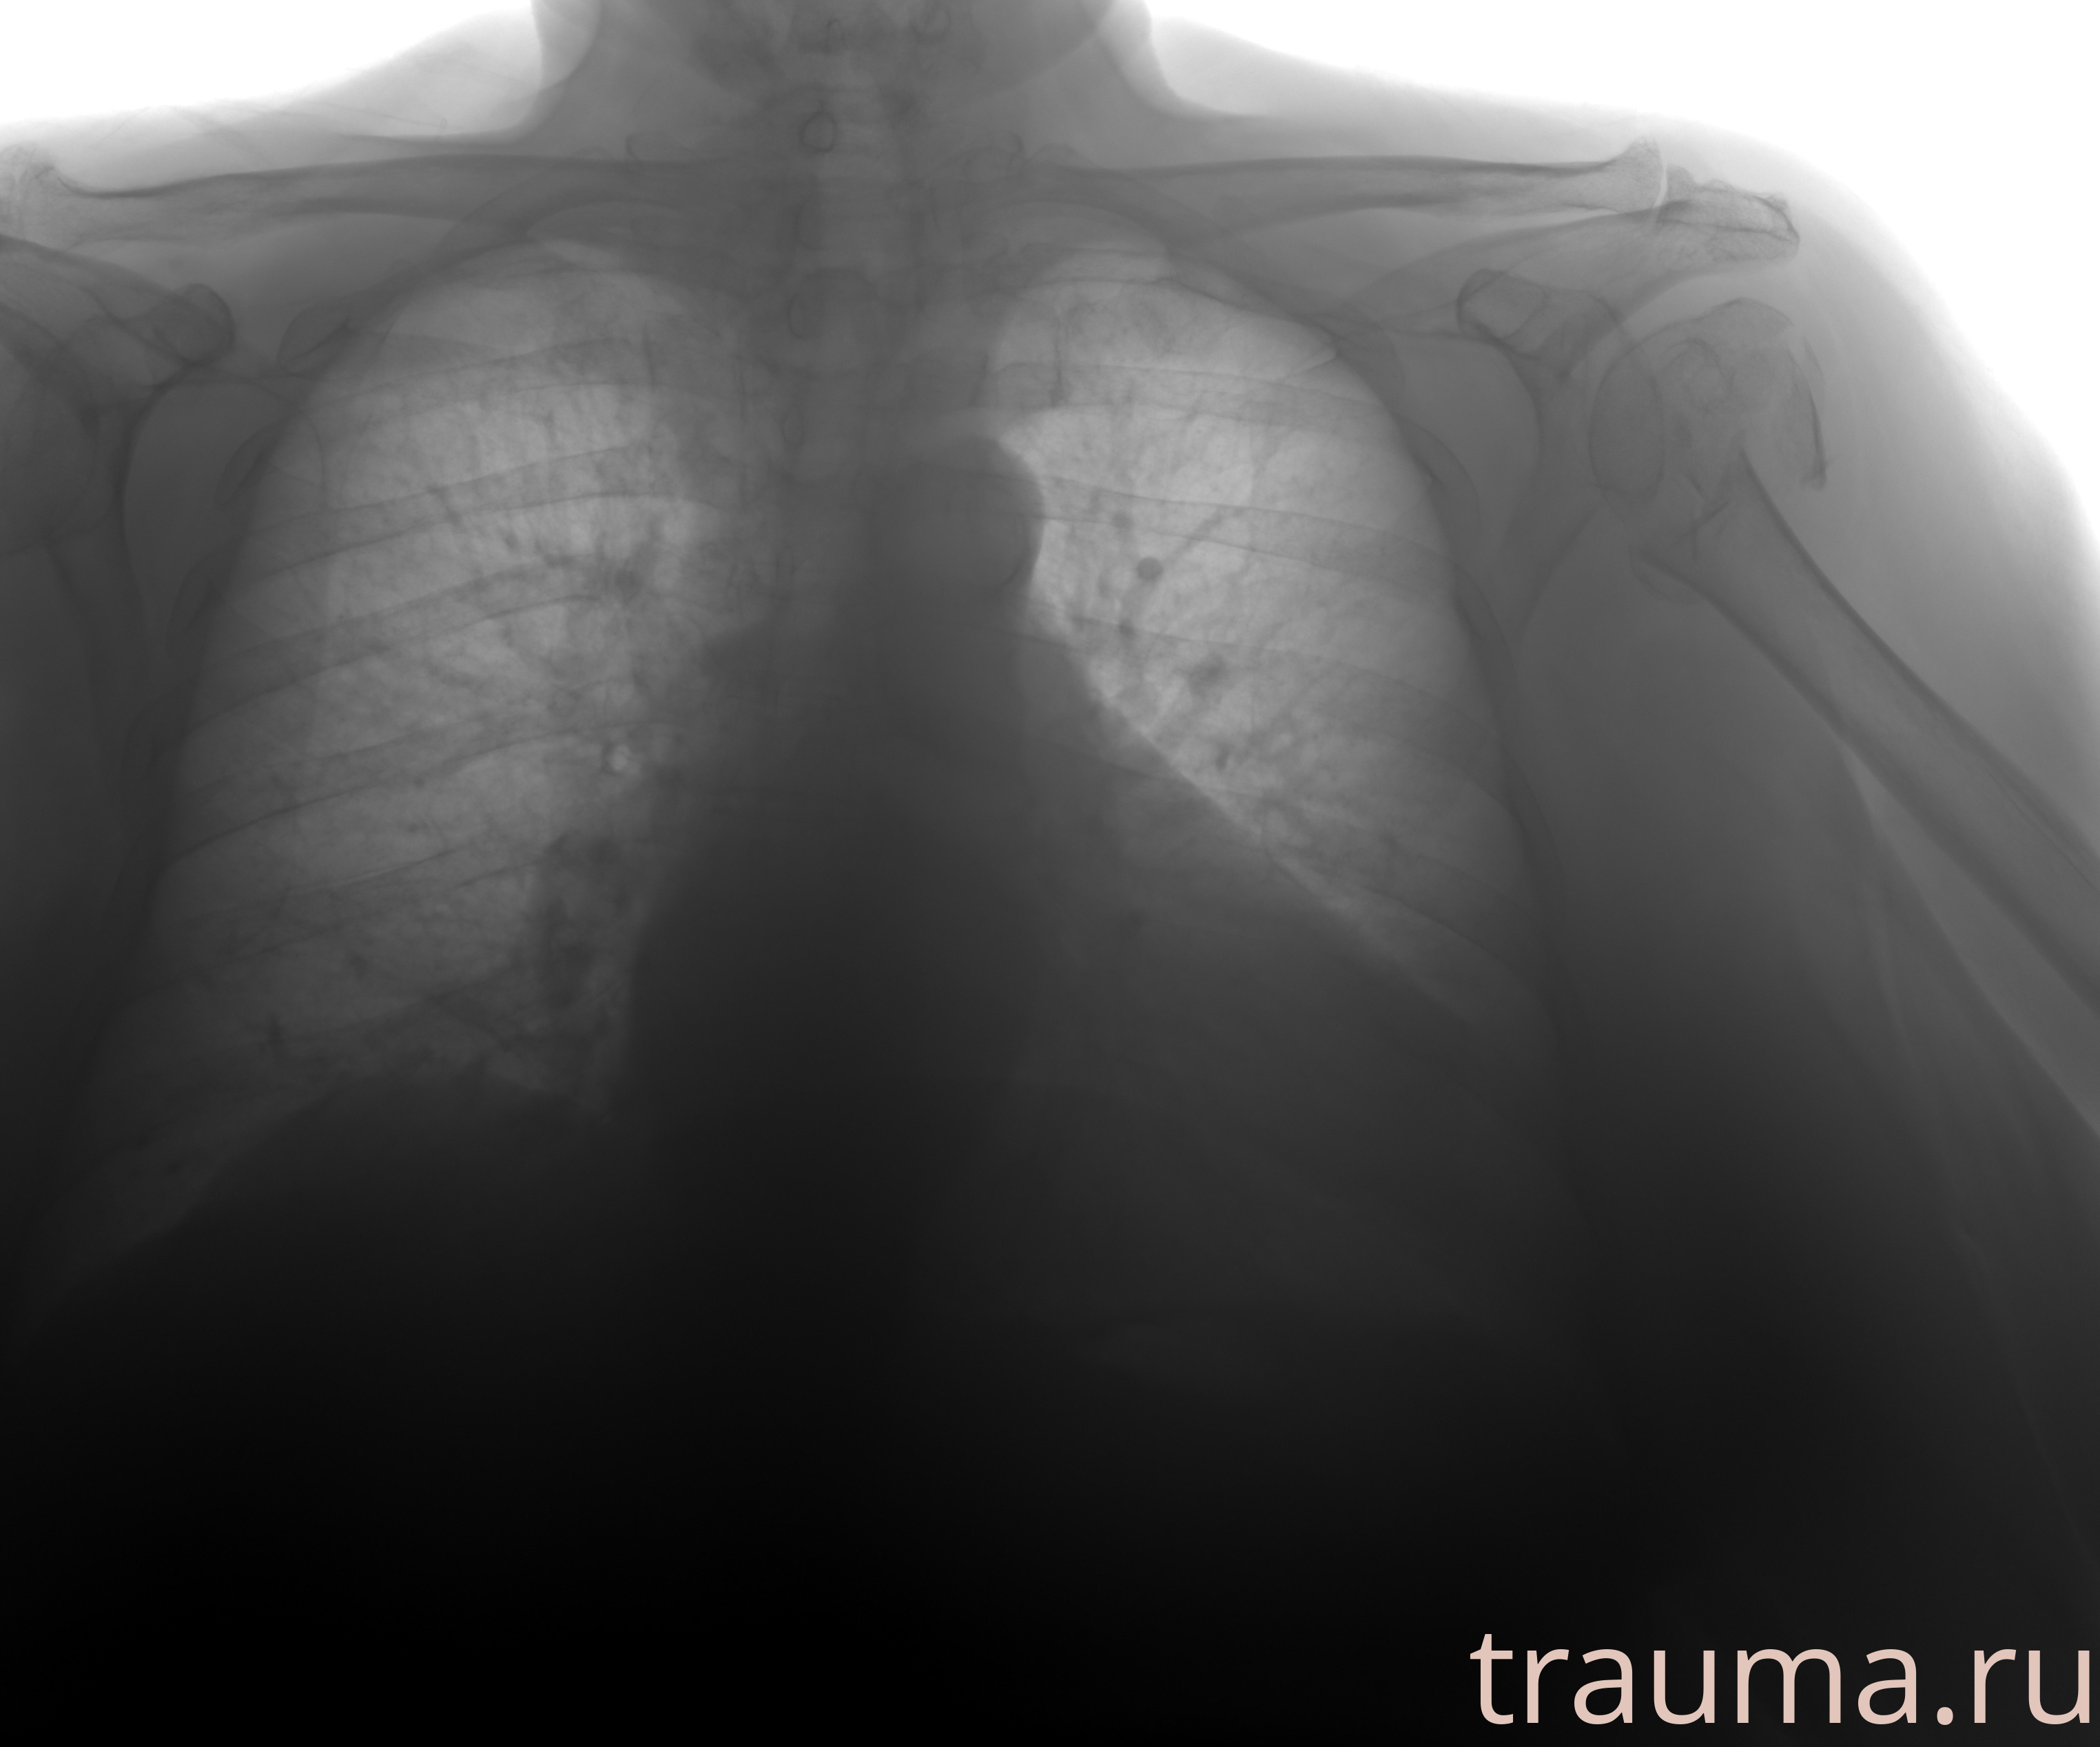

Рентгенограммы

Рентген на дому: по вашему адресу приезжает врач-рентгенолог, травматолог-ортопед с мобильным рентгеновским аппаратом, проводит диагностику травмы или заболевания, делает необходимые рентгенограммы, дает рекомендации по дальнейшему лечению. Получить качественные снимки в домашних условиях возможно благодаря уникальной методике, разработанной МосРентген Центром для института  Склифосовского